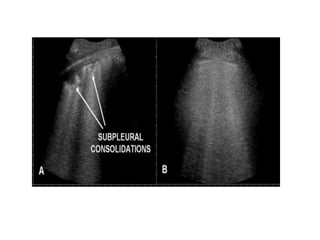

Pulmonary Embolism

Schematic representation of the parenchymal, pleural and vascular

features associated with pulmonary embolism.(Angelika Reissig, Claus

Kroegel. Respiration2003;70:441-452)

Schematic representation ofthe parenchymal, pleural and vascular features associated with pulmonary embolism.(Angelika Reissig, Claus Kroegel. Respiration2003;70:441-452)